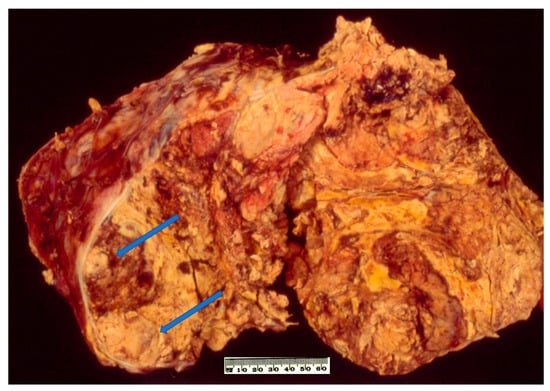

2.3. Pathology

6. Sarcomatoid Adrenocortical Carcinoma

6.3. Pathology